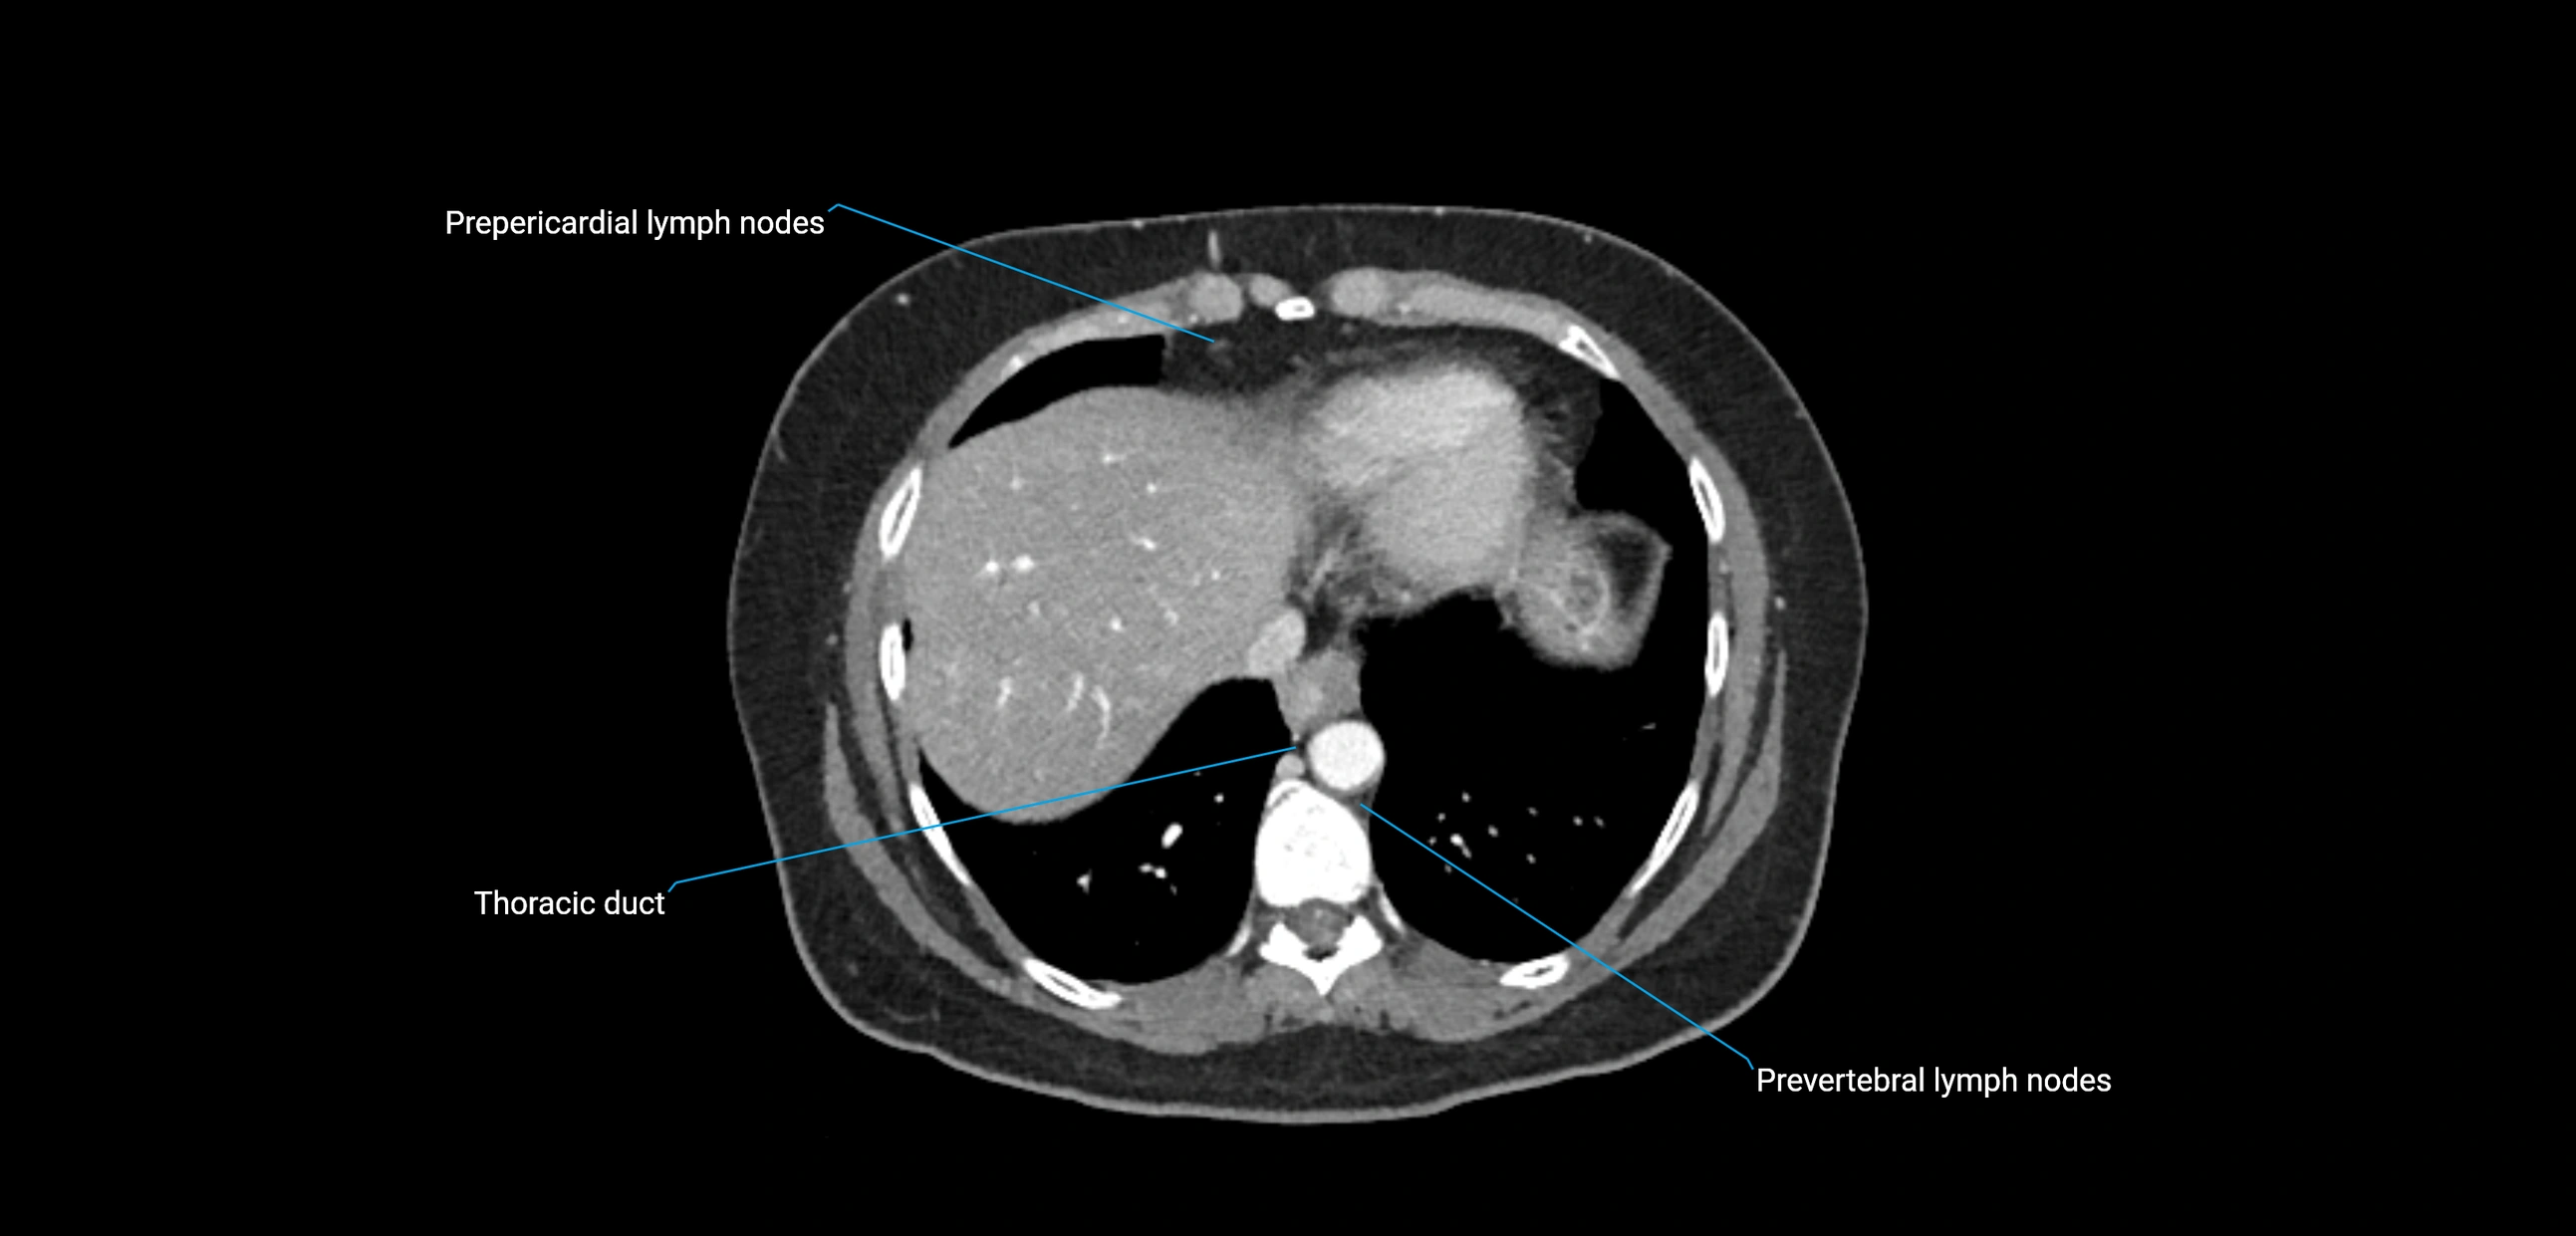

CT image

image